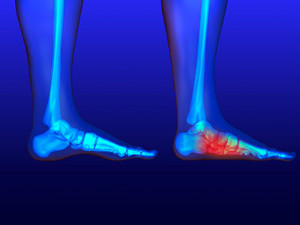

What to Know About a Broken Toe

Trauma to the foot, especially the toes, can occur in many ways. Banging them, stubbing them, or dropping something on them are a few different ways this trauma can occur. Given the fact that toes are positioned in front of the feet, they typically sustain the brunt of such trauma. When trauma occurs to a toe, the result can be a painful break or fracture. Another type of trauma that can break a toe is repeated activity that places stress on the toe for prolonged periods of time.

Broken toes can be categorized as either minor or severe fractures. Symptoms of minor toe fractures include throbbing pain, swelling, bruising on the skin and toenail, and the inability to move the toe with ease. Severe toe fractures require medical attention and are indicated when the broken toe appears crooked or disfigured, when there is tingling or numbness in the toe, or when there is an open, bleeding wound present on the toe.

Generally, a minor toe break will heal without long-term complications. However, it is important to discontinue activities that put pressure on the toe. It is best to stay off of the injured toe and immediately get a splint or cast to prevent any more additional movement of the toe bones. You can also immobilize your toe by placing a small cotton ball between the injured toe and the toe beside it. Then, tape the two toes together with medical tape. Swelling can be alleviated by placing an ice pack on the broken toe directly as well as elevating your feet above your head.

Severe toe fractures may be treated with a splint, cast, and in some cases, minor surgery, especially when the big toe has been broken. Due to its position and the pressure the big toe endures with daily activity, future complications can occur if it is not properly treated. Pain associated with minor toe fractures can be managed with over-the-counter pain medications. Prescription pain killers may be necessary for severe toe fractures.

The healing time for a broken toe is approximately four to six weeks. In severe cases where the toe becomes infected or requires surgery, healing time can take up to eight weeks or more. While complications associated with a broken toe are immediately apparent, it is important to note that there are rare cases when additional complications, such as osteoarthritis, can develop over time. You should immediately speak with your podiatrist if you think you have broken your toe due to trauma. They will be able to diagnose the injury and recommend the appropriate treatment options.